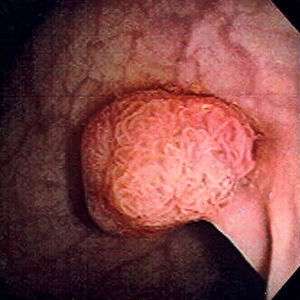

| Colon polyps | |

| Polyp of sigmoid colon as revealed by colonoscopy. Approximately 1 cm in diameter. The polyp was removed by snare cautery | |